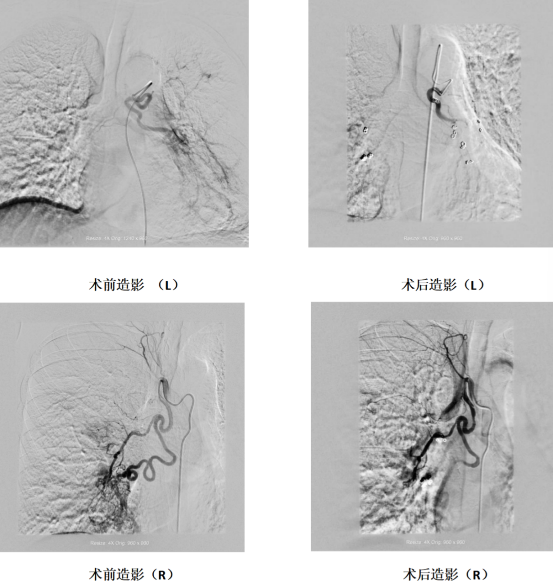

3天前,冯阿姨晨起咳痰见血丝,没成想很快发展成大口咯血。家人将冯阿姨紧急送往西安大兴医院渭水园院区后,介入血管科于黎明主任团队接诊后,立即启动介入导管室。术前CTA检查显示其支气管动脉严重迂曲扩张,术中更发现支气管动脉-静脉瘘——这正是咯血的“元凶”。

术前CTA与术中DSA影像精准配准,3D Fusion技术让迂曲血管立体呈现,Overlay技术将血管走形叠加在实时画面上——原本“盲探”的出血点,瞬间“一眼锁定”。微导管在导航引导下快速且精准到达靶血管,快速注入栓塞剂顺利止血。在医技护团队的共同努力下,从入院到止血结束,全程仅用 45 分钟,较传统手术缩短近2小时。